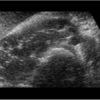

– Thận xoa trục, 2 cực dưới thận liên tục với nhau vắt ngang qua phía trước cột sống bởi nhu mô thận hay tổ chức xơ.

– Trên lát cắt dọc: không thấy rõ ranh giới cực dưới 2 thận.

– Trên lát cắt ngang qua đường giữa: 2 thận dính nhau, vắt ngang qua cột sống, phía trước động mạch chủ bụng.

– Có thể kèm theo các bất thường bất thường đường bài xuất, thận đôi, sỏi, nang thận hoặc u thận, sỏi gây giãn đường bài xuất.

=> Case lâm sàng 2: